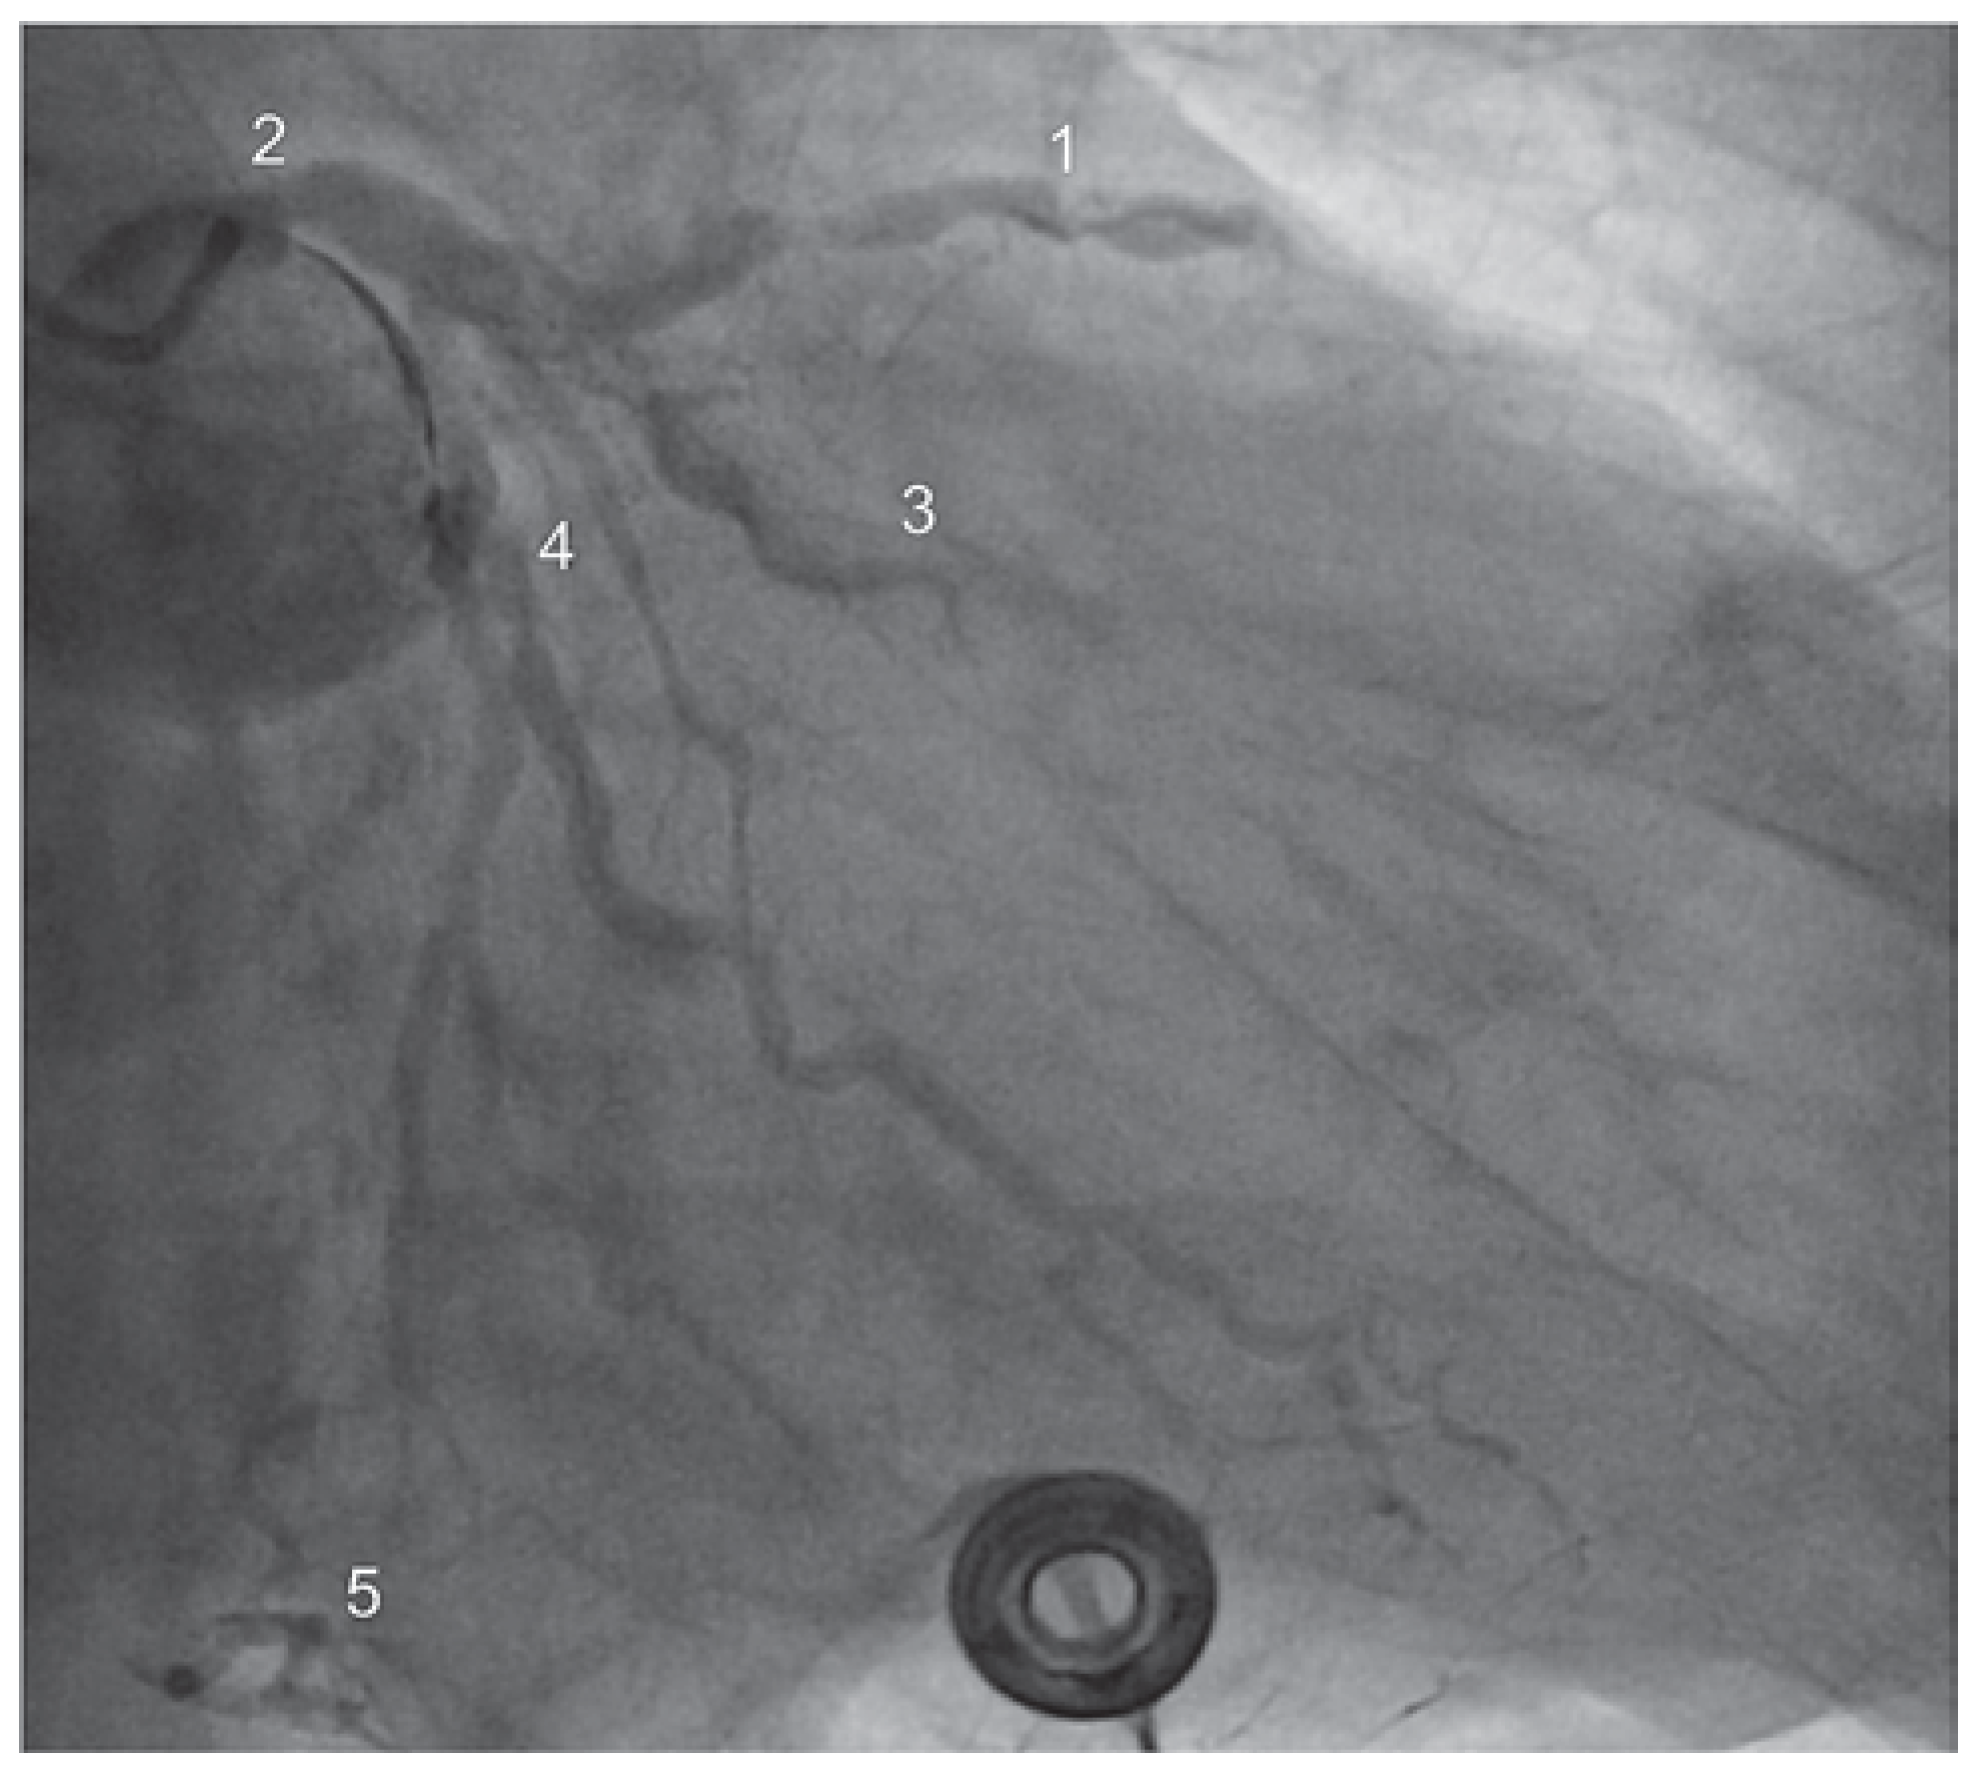

Die Zuweisung des 75-jährigen Patienten erfolgte durch ein Regionalspital mit dem Bild eines subakutem Nicht-ST-Hebungsinfarktes und beginnendem kardiogenem Schock (Killip Klasse III-VI). Die Labordiagnostik zeigte erhöhte Herzenzyme (hochsensitives Troponin 0,7). Die Koronarangiographie ergab eine schwere koronare 2-Gefäss-Erkrankung mit Hauptstammbeteiligung (90% Stenose des distalen Hauptstamms sowie Verschluss des proximalen RCX und 70% Stenose des proximalen RIVA) (Abbildung 3). Bei kleiner rechter Koronararterie liess sich zudem ein Linksversorgertyp identifizieren.

Abbildung 3. Koronarangiographie vor Intervention – Fall 2. 1 – RIVA, 2 – Hauptstamm, 3 – RCX.